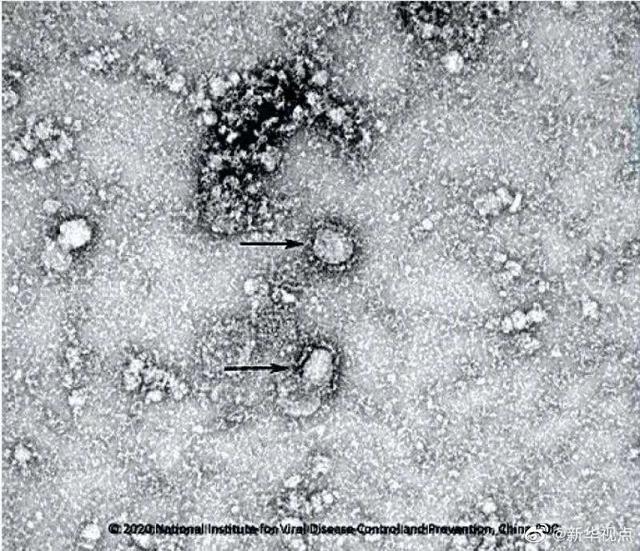

金奇介绍说 , 近日 , 中国医学科学院病原生物学研究所在对第三方检测机构提供的患者样本宏基因组测序序列信息分析的基础上 , 指导完成病毒全基因组序列的测定 , 结果证明样本中存在一种未知的、不同于SARS冠状病毒和MERS冠状病毒的新型冠状病毒 , 为最终确定此次疫情的病因做出了重要贡献 。

“由于新型冠状病毒在演化关系上最为接近的类群 , 都能在各类蝙蝠中发现 , 因此推测新型冠状病毒的原始宿主也可能是蝙蝠 。 ”金奇说 。

1月23日 , 研究人员利用提取的nCoV-2019全基因组序列 , 与从人类和不同动物身上发现的SARS病毒和冠状病毒进行了基因和功能的比较分析 。 不同种冠状病毒的系统发育分析表明 , 2019-nCoV可能起源于蝙蝠 , 但目前尚不清楚中间传播媒介 。 2019-nCoV的S蛋白与人类SARS病毒P2的同源性约为76% , 与蝙蝠SARS样病毒的同源性较高 , 与最接近蝙蝠冠状病毒、蝙蝠冠状病毒BM48-31的同源性为72% , 与其他蝙蝠冠状病毒的同源性更低 。 这些数据进一步表明2019-nCoV更可能是一种与SARS病毒仅有松散联系的新型蝙蝠冠状病毒 。